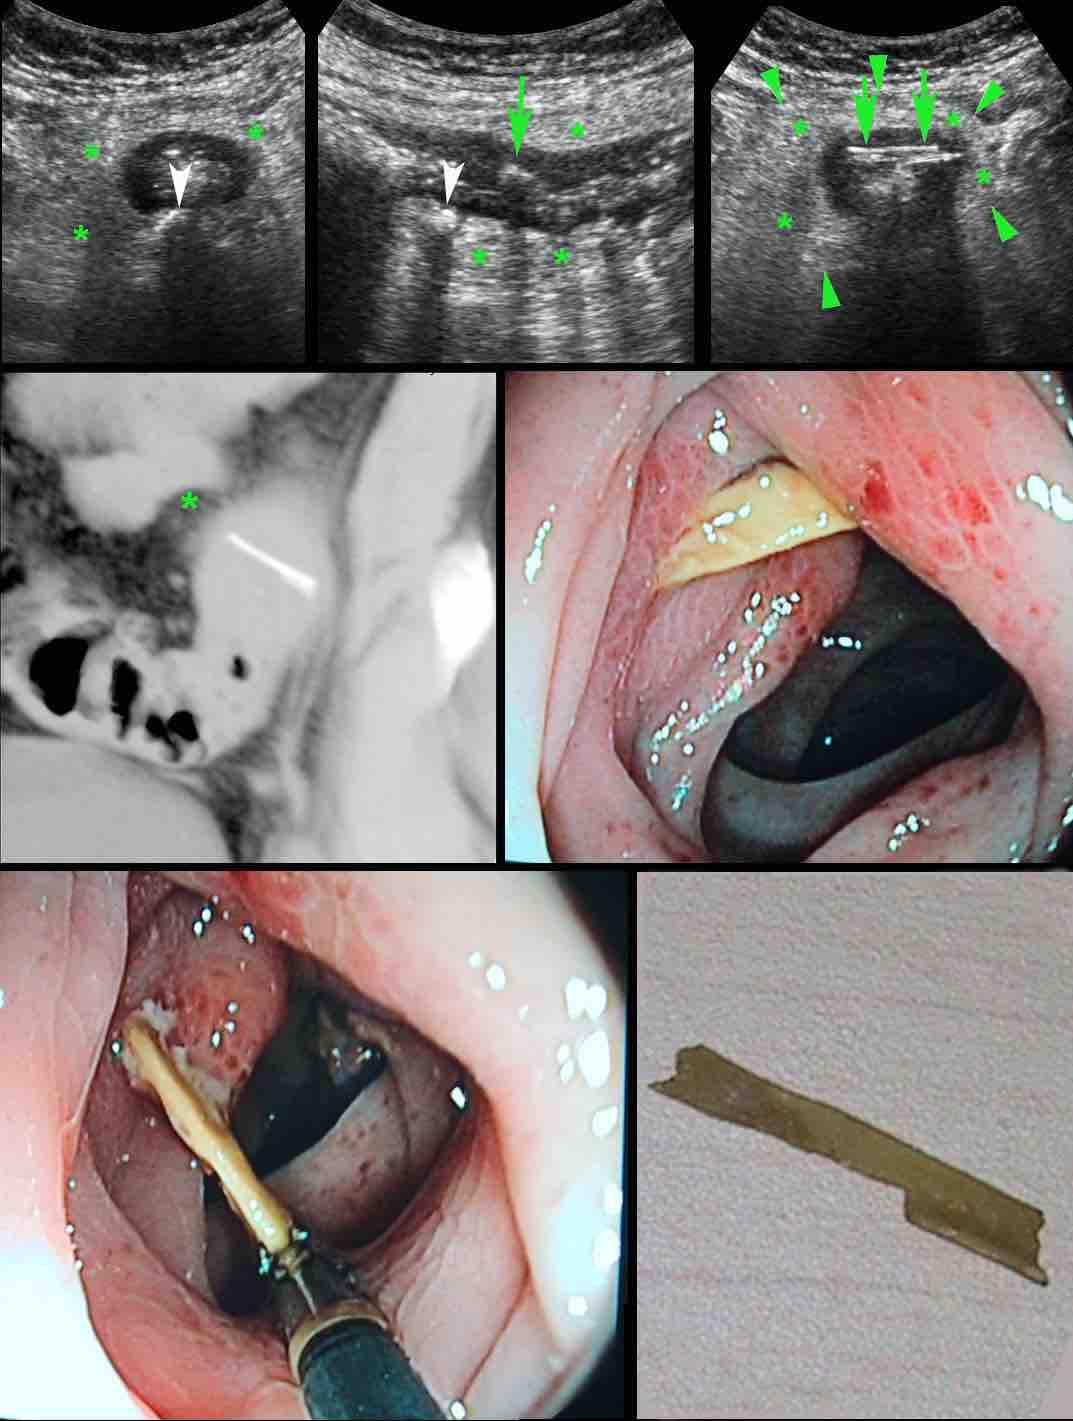

Bệnh nhân nam 53 tuổi nhập viện với khối đau hố chậu trái và CRP 173, nghi ngờ viêm túi thừa.

Bệnh nhân có tiền sử cắt thận trái 20 năm trước.

Siêu âm phát hiện áp xe thành bụng chứa một cấu trúc mỏng, đường cong (mũi tên).

CT không và có tiêm thuốc cản quang tĩnh mạch xác nhận xương cá (mũi tên) trong áp xe thành bụng có ranh giới không rõ ràng.

Lưu ý rằng xương cá có thể dễ dàng bị bỏ sót nếu chỉ chụp CT có tiêm thuốc cản quang tĩnh mạch.

Vị trí áp xe và xương cá được đánh dấu trên da.

Chỉ với một đường rạch rất nhỏ, mủ và xương cá đã được lấy ra. Hồi phục không biến chứng.

Bệnh nhân nữ người Suriname trẻ (31 tuổi) với đau hố chậu trái 3 tuần và CRP 55, nghi ngờ viêm phần phụ hoặc viêm túi thừa.

Tiền sử vỡ tử cung.

Siêu âm cho thấy khối giảm âm bên trái tử cung (u.) nghi ngờ áp xe vòi trứng-buồng trứng (TOA).

Ở ngoại vi thấy một phản âm mỏng, đường cong (mũi tên).

Siêu âm qua đường âm đạo xác nhận xương cá (mũi tên) trong thành của TOA.

CT không tiêm thuốc cản quang cho thấy TOA có liên quan mật thiết với đại tràng sigma, vốn cũng có dày thành khu trú.

Trong phẫu thuật, TOA và xương cá dính chặt vào đại tràng sigma đã được lấy ra.

Rõ ràng, xương cá sau khi xuyên thủng đại tràng sigma đã di chuyển vào buồng trứng trái, gây ra TOA.

Lưu ý màu xanh lá của xương cá, có thể do sắc tố mật.